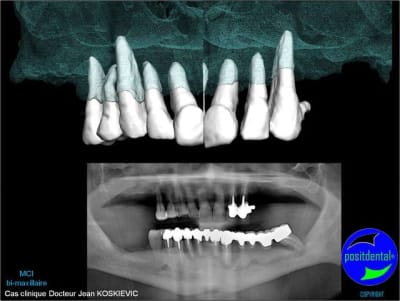

Je viens de recevoir les empreintes pour réaliser un Positscan en prévision d'une MCI bi-maxillaire. "chouette" un peu de métal pour corser l'histoire.

3D maxillaire inférieur et photo

Montage esthétique ou wax-up 3D